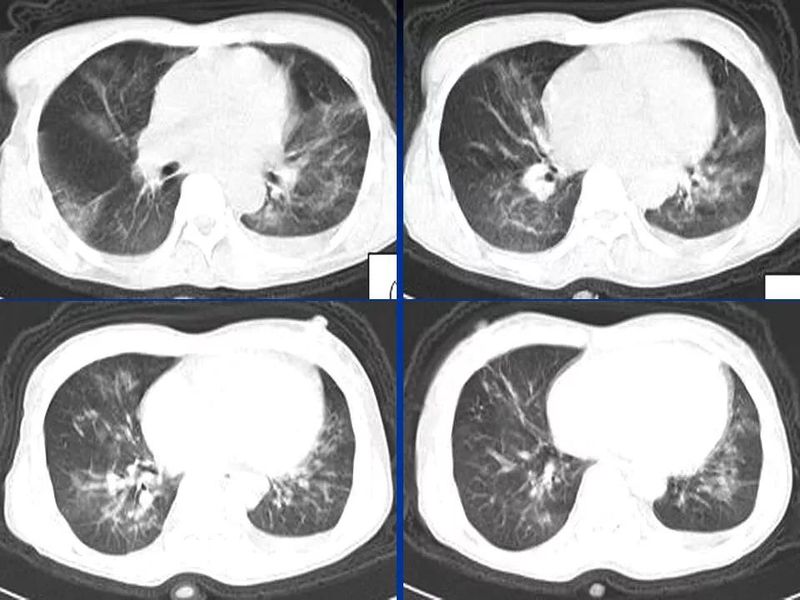

主任提醒:这个病很容易误诊为肺炎!